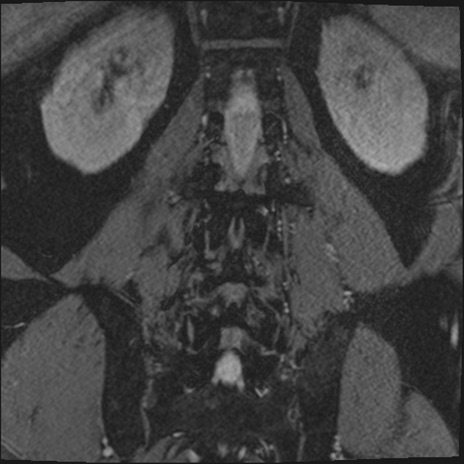

【整形】TIPS症例2 腰椎MRI 3D(冠状断像)

【症例】70歳代男性

【主訴】左下肢痛

【現病歴】2週間前くらいから腰痛、左下肢痛あり。左臀部から大腿、下腿外側のしびれが常時ある。歩行とともに同部位の痛みあり。

【身体所見】Lasegue70-/60+、Bragard-/±、PTR ±/±、ATR -/-、IP 5/5、TA 5/4、TS 5/5、EHL 右第1足趾なし/3、FHL 5/5、hypersthesia(-)、足背動脈触知良好

異常所見と診断は?